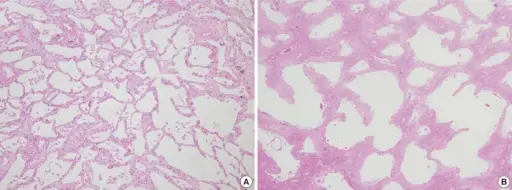

Bronchopneumonia is characterized by patchy, sporadic consolidation, concentrated on the bronchioles.

Bronchopneumonia is frequently bilateral and multifocal.

Bronchopneumonia is caused by different bacterial species.